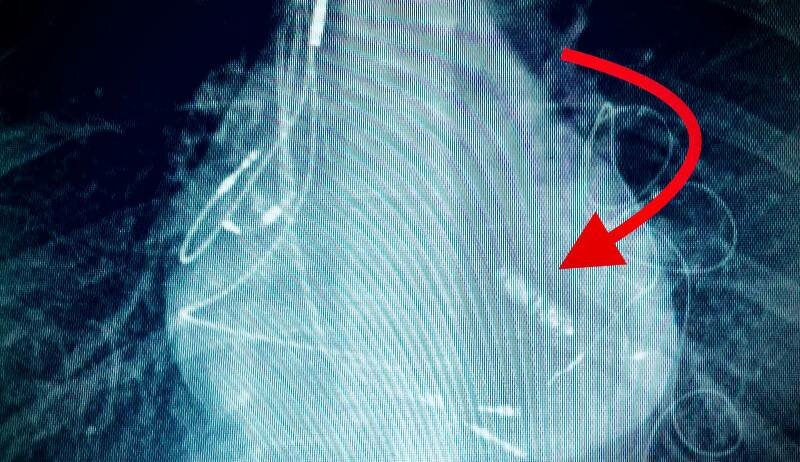

E' stato il primo intervento di questo tipo in Italia. Sei gli elettrodi nel cuore, tutti malfunzionanti, la cui estrazione avrebbe richiesto un intervento in circolazione extracorporea, ovvero un intervento a cuore aperto, con rischio consistente per le numerose procedure chirurgiche già effettuate e per le diffuse aderenze che gli elettrodi contraggono con le vene del paziente. Queste le motivazioni che hanno spinto l’equipe medica - composta dall’elettrofisiologo Rosario Foti, dai cardiologi e cardiochirurghi pediatrici Paolo Guccione e Salvatore Agati, coordinata dal dottor Ludovico Vasquez, responsabile della cardiologia dell’ospedale San Vincenzo di Taormina - a utilizzare un pacemaker senza elettrodi. Il Micra “è infatti un pacemaker miniaturizzato che viene impiantato in ventricolo destro sul setto interventricolare e non necessita di elettrodi che sono invece necessari nell’usuale impianto di pacemaker; il suo design è tale da minimizzare il rischio di dare fastidio alle altre strutture del cuore. Il dispositivo viene agganciato con dei piccoli uncini al muscolo del setto inter-ventricolare e ha la capacità di ripristinare la fisiologica attivazione elettrica del cuore. Il Micra capta l’attività elettro-meccanica elettricità della parte alta del cuore (atrii) e la trasmette alla parte bassa (ventricoli) in modo coordinato. La batteria garantisce una stimolazione del cuore per 10/12 anni". L’intervento durato circa 90 minuti è stato realizzato in anestesia locale. Attraverso le vene dell’inguine il pacemaker Micra è stato portato in ventricolo destro e quindi agganciato al miocardio del setto interventricolare. L’impianto del Micra ha determinato il ripristino della fisiologica attivazione del cuore con una frequenza cardiaca compresa tra 70 e 90 battiti per minuto alleviando i sintomi e consentendo al paziente di lasciare l’ospedale già il giorno successivo all’intervento.